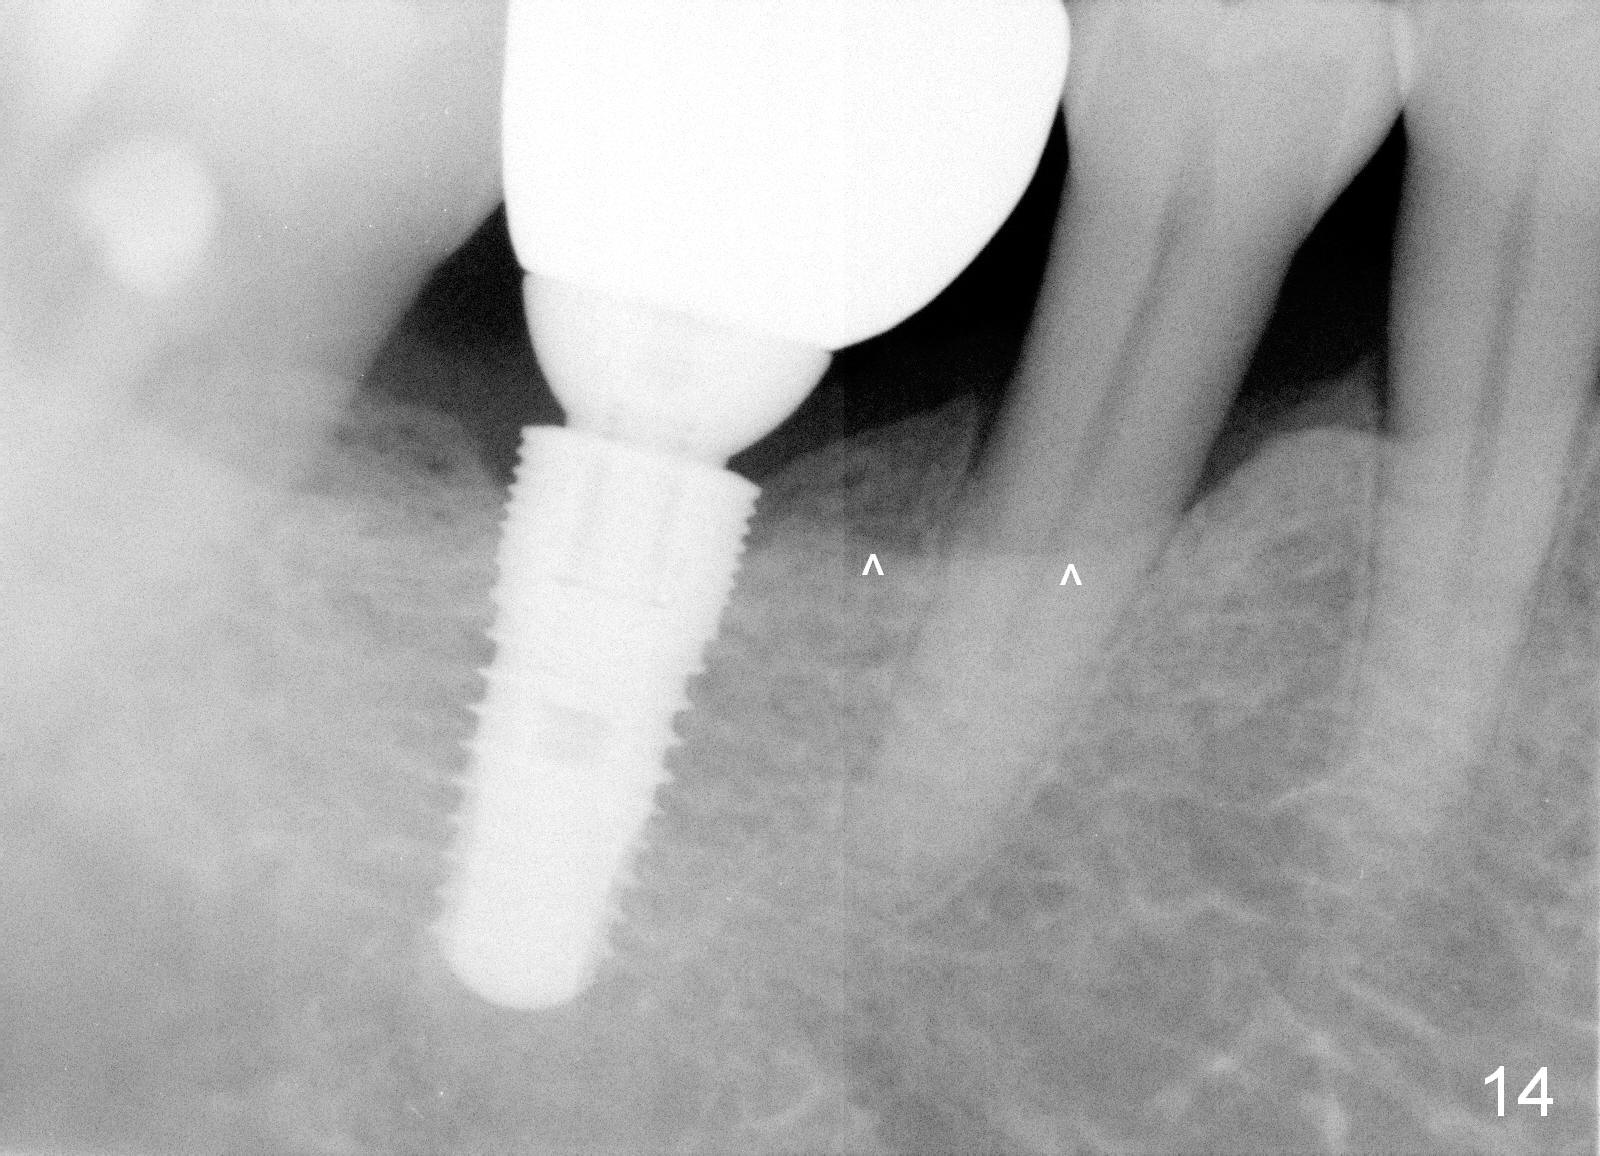

The patient returns for recall 9 months post cementation. His concern is inability to masticate hard on the right side. The tooth #29 has mobility I with bone loss (Fig.14 ^). Six months later, the symptom disappears. In fact occlusal equilibrium should be provided. There is no bone loss 2 years 2 months post cementation (Fig.15).